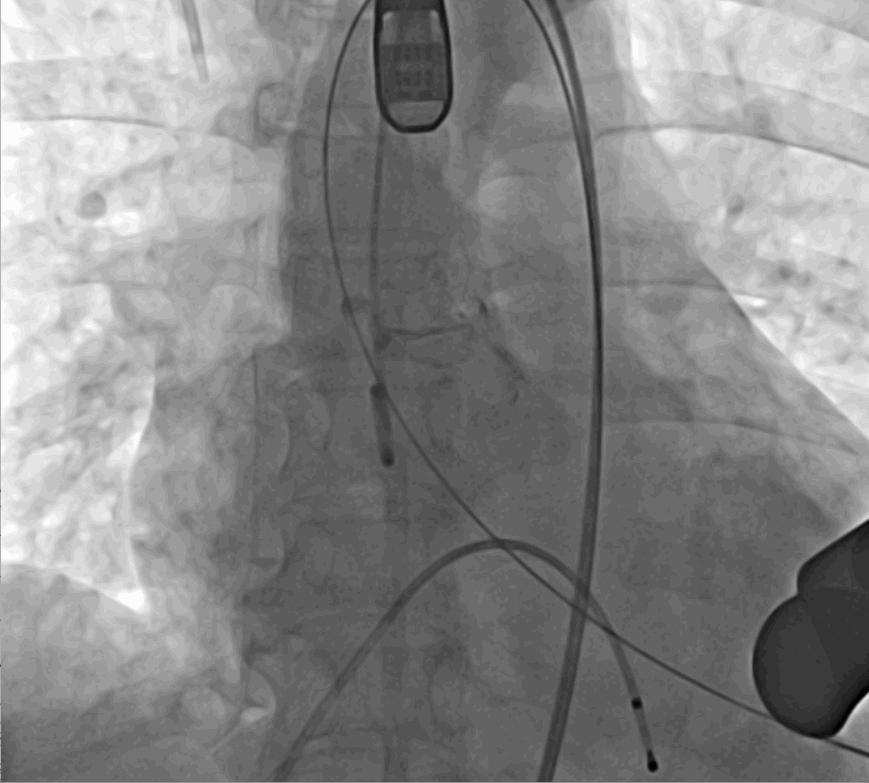

術(shù)前DSA影像圖

手術(shù)采用經(jīng)心尖入路,對患者進(jìn)行全麻后,在左側(cè)心尖處做3-4cm微創(chuàng)手術(shù)切口,在DSA及超聲引導(dǎo)下手術(shù)順利完成。從導(dǎo)入器械到完成瓣膜置入,僅耗時約10分鐘。術(shù)后即刻主動脈瓣返流程度由術(shù)前大量返流轉(zhuǎn)為消失,患者于導(dǎo)管室拔除氣管插管,次日由ICU轉(zhuǎn)入普通病房。